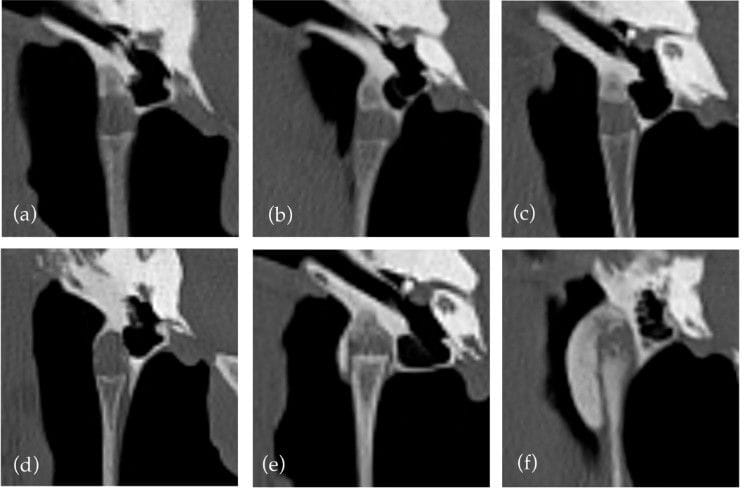

An illustration of the grades of temporohyoid joint. (a) Grade 0 shows no new bone formation. (b–d) all show Grade 1 temporohyoid joints; however, they illustrate the variation within this grade; (b) shows new bone formation not crossing the joint, while (c,d) show different degrees of new bone formation both crossing the medial aspect of the joint. (e) Grade 2. (f) Grade 3.